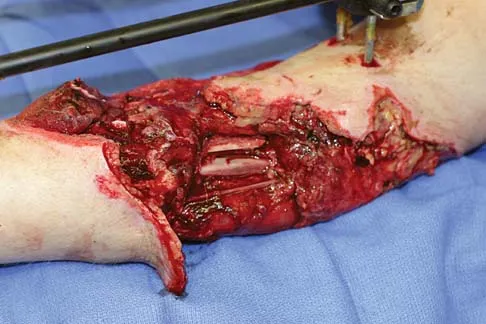

A healthy 25-year-old man sustains a grade IIIB open tibial fracture. Following appropriate debridement, irrigation, and stabilization with an external fixator, the soft-tissue injury is shown in Figure 30. What is the most appropriate definitive soft-tissue coverage procedure?

Explanation

This is a very large near circumferential defect with posterior as well as anterior skin and muscle injury. Bone is exposed. The posterior muscles cannot be rotated since they are part of the zone of injury. The bone and other poorly vascularized areas of this wound would not accept a skin graft. The best chance for limb salvage will be to obtain soft-tissue coverage with a free tissue transfer using the latissimus dorsi. Mathes SJ, Nahai F: Vascular anatomy of muscle: Classification and applications, in Mathes SJ, Nahai F (eds): Clinical Application for Muscle and Musculocutaneous Flaps. St Louis, MO, CV Mosby, 1982, p 20.

- Bos GD, Buehler MJ: Lower-extremity local flaps. J Am Acad Orthop Surg 1994;2:342-351.